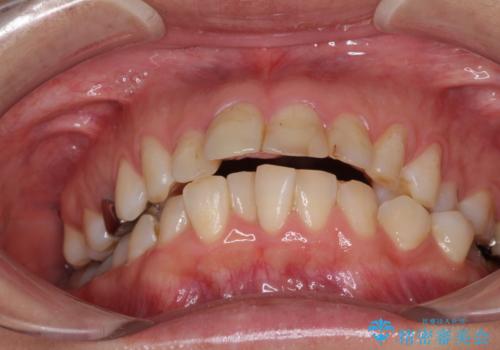

- 前歯のデコボコと前方に斜めに飛び出した前歯を気にして来院された患者様です。

口元の突出感はあまり気になっていませんでしたが、上下の前歯の前後差が大きかったため、上顎左右の第一小臼歯を抜歯し、上顎が裏側装置であるハーフリンガルにて矯正治療を行うこととしました。

咬合力が非常に強く、スペースがなかなか閉じなかったことと、上下の正中が著しくずれてきてしまったため、下顎左側小臼歯を途中抜歯することとなりました。